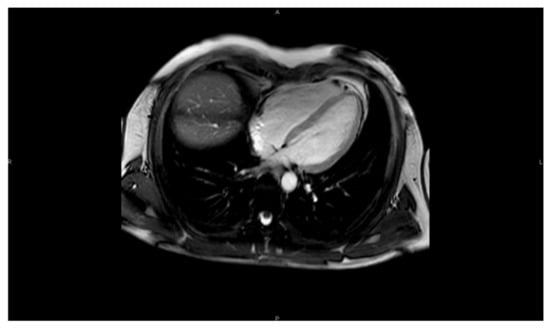

4. Cardiac Magnetic Resonance (CMR)

Cardiac magnetic resonance imaging (CMR) exploits the capacity of hydrogen protons that are abundant in the water and in the fat of biological tissues to absorb radiofrequency energy when placed in an external magnetic field. As a result, an evolving spin polarization can induce a signal in a radiofrequency coil, to be detected by antennas and after signal analysis to reconstruct high-resolution images. The most common CMR sequences are T1-weighted and T2-weighted scans in which we can measure very accurately left and right ventricular volumes, ventricular mass, atrial volumes, and vessel dimensions [15].

4.1. T1-T2–LGE

One of the main advantages of CMR over other imaging techniques relies on myocardial tissue characterization. T1-weighted sequences are very useful to visualize cardiac anatomy in great detail and detect the presence of intra-myocardial fat. T1 mapping can also quantify myocardial fibrosis [16]. For the detection of myocardial edema, the best modality is the use of T2-weighted imaging. Additionally, the use of contrast agents such as gadolinium can significantly increase the diagnostic capacities of CMR (Figure 9 and Figure 10). Late gadolinium enhancement (LGE) is a useful tool for the proper identification of infarcted myocardium. This technique is mainly used along with perfusion CMR to assess whether a wall region in question is ischemic or infarcted (scar) [17,18].

Further functional and structural information can be acquired thanks to the development of a magnetic resonance sequence called balanced steady-state free precession (bSSFP) cine imaging. They are usually retrospectively gated and have intrinsically high contrast. Images are typically planned sequentially to achieve the standard cardiac planes to access left and right ventricular size and function and can be played in video mode which allows evaluation of biventricular volume, mass, and EF with valvular motion [16,17,18].

Figure 9. CMR image 4CH view of the heart.

Figure 10. CMR image 2CH view.